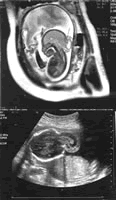

图1 枕部脑膜脑膨出MRI图像

矢状面,示枕部一混杂信号包块,内有呈高信号的脑脊液和呈等信号的脑组织通过局部颅骨的缺损与颅内相连。

图2 枕部脑膜脑膨出的轴面US图像